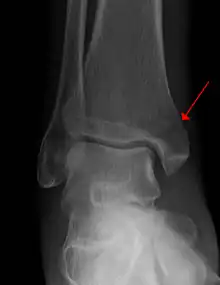

Example of an intraarticular fracture of the medial malleolus extending in the talocrural ankle joint | |

An intraarticular fracture is a bone fracture in which the break crosses into the surface of a joint. This always results in damage to the cartilage.[1] Compared to extraarticular fractures, intraarticular have a higher risk for developing long-term complications, such as posttraumatic osteoarthritis.[2]